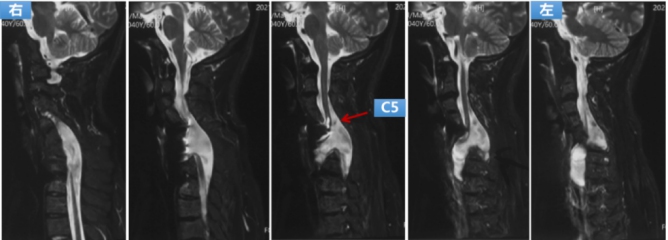

Preoperative MRI: the dura mater and spinal cord herniated from the defected bone to the front of the vertebral body to the left, which shows spinal cord compression and ischemic degeneration.